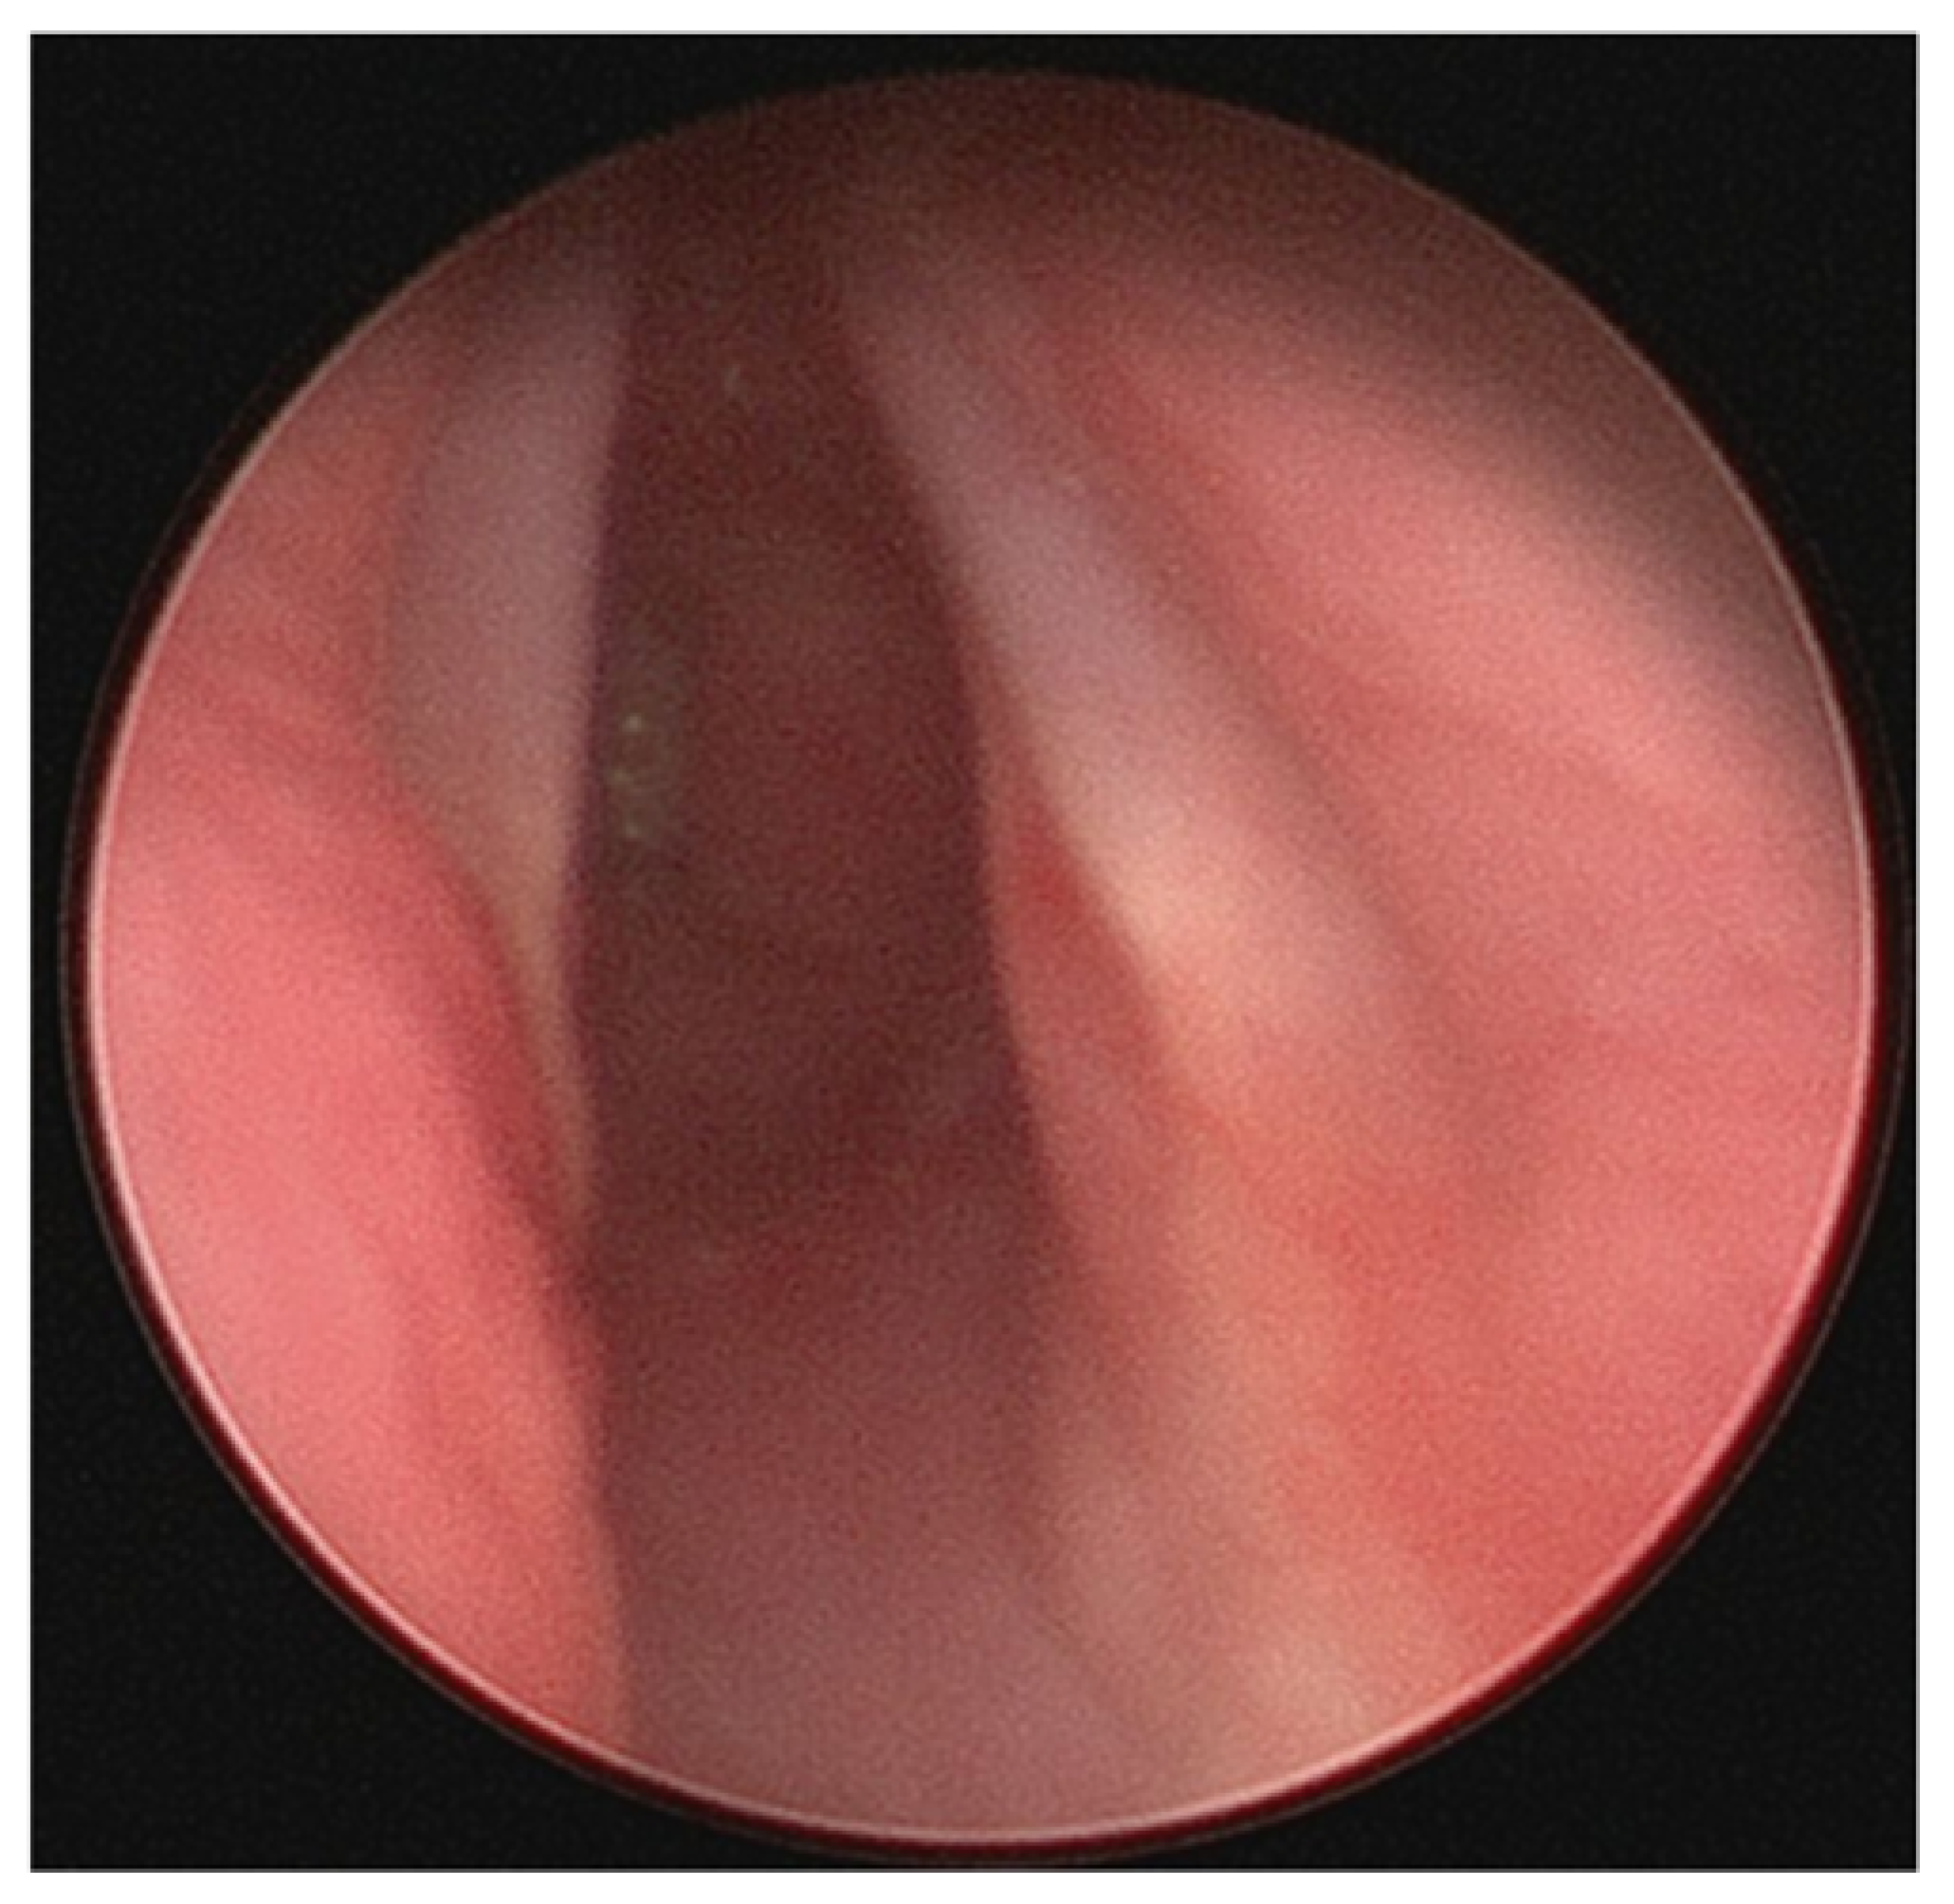

2.3. Subglottic Stenosis